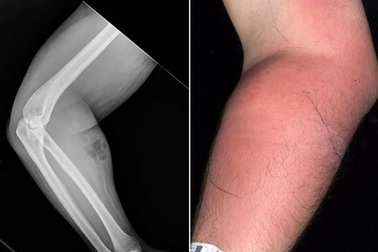

Người đàn ông tự tiêm… tinh trùng để chữa đau lưngMột người đàn ông giấu tên người Ailen với cánh tay sưng phồng được phát hiện đã tự tiêm tinh trùng của chính mình để chữa bệnh tại nhà.